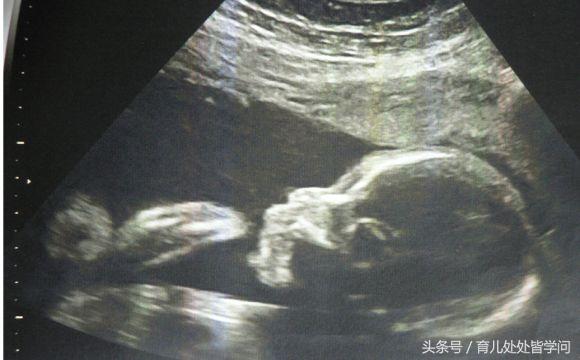

胎儿从卵泡到性别形成17张图片清晰诠释男宝女宝看得很清楚

广州妈妈告诉你两张b超图片便可提前知道是男是女